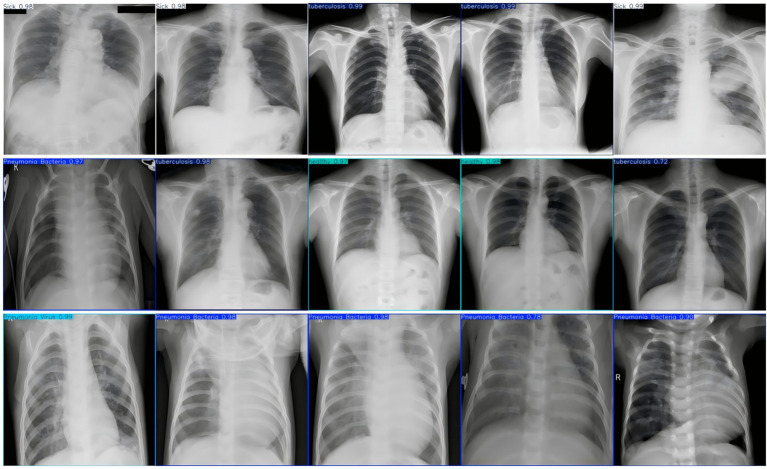

Early and accurate diagnosis of pneumonia is crucial to improve cure rates and reduce mortality. Traditional chest X-ray analysis relies on physician experience, which can lead to subjectivity and misdiagnosis. To address this, we propose a novel pneumonia diagnosis method using the Fast-YOLO deep learning network that we introduced. First, we constructed a pneumonia dataset containing five categories and applied image enhancement techniques to increase data diversity and improve the model's generalization ability. Next, the YOLOv11 network structure was redesigned to accommodate the complex features of pneumonia X-ray images. By integrating the C3k2 module, DCNv2, and DynamicConv, the Fast-YOLO network effectively enhanced feature representation and reduced computational complexity (FPS increased from 53 to 120). Experimental results subsequently show that our method outperforms other commonly used detection models in terms of accuracy, recall, and mAP, offering better real-time detection capability and clinical application potential.

Abstract Image